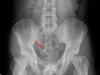

65歲的簡女士C肝病史近20年,早年接受干擾素治療,以為自己「好了」,卻不知道病毒一直跟著她,直到半年前莫名疲勞,一天要睡16、7小時,加上某天突然手麻跌到,以為是中風就醫,才知C肝不但沒好,甚至演變成嚴重肝硬化,在超音波下肝臟看起來像「苦瓜」。

簡女士表示,她去年底確診出1b型C肝後,今年1月透過醫院申請到C肝口服抗病毒藥物,現在不僅測不到病毒,超音波檢查肝臟也變得比較「平整」,主治醫師、台北榮總健康管理中心主任王苑貞表示,簡女士治療3個月後,病毒指數已從500萬IU/ml降到幾乎測不到,成功根除C肝。